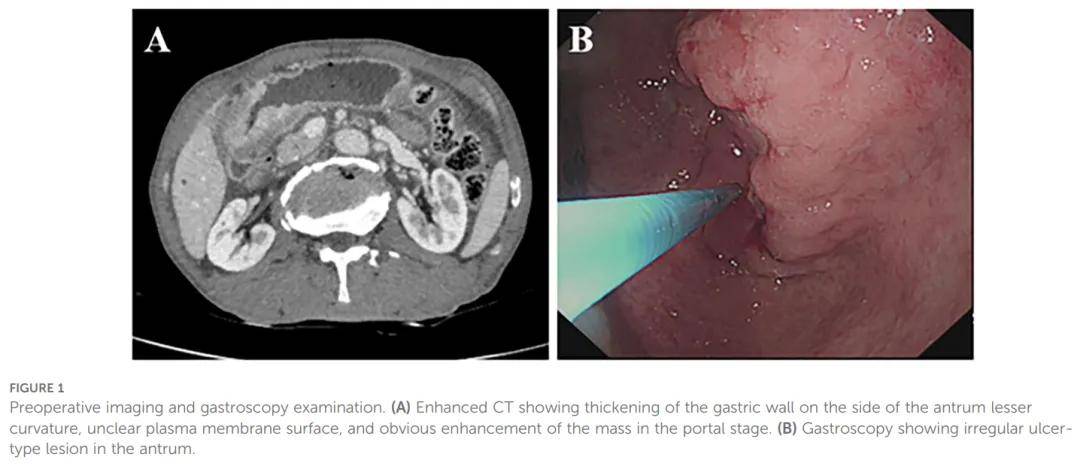

胃腺鳞癌(ASC)是一种极其罕见的肿瘤。其罕见性导致有关其诊断和管理的文献稀少,给临床实践带来了相当大的挑战。一名 70 岁男性因上腹痛就诊,胃镜和CT检查发现胃窦部肿块。组织病理学分析确诊为腺鳞癌。